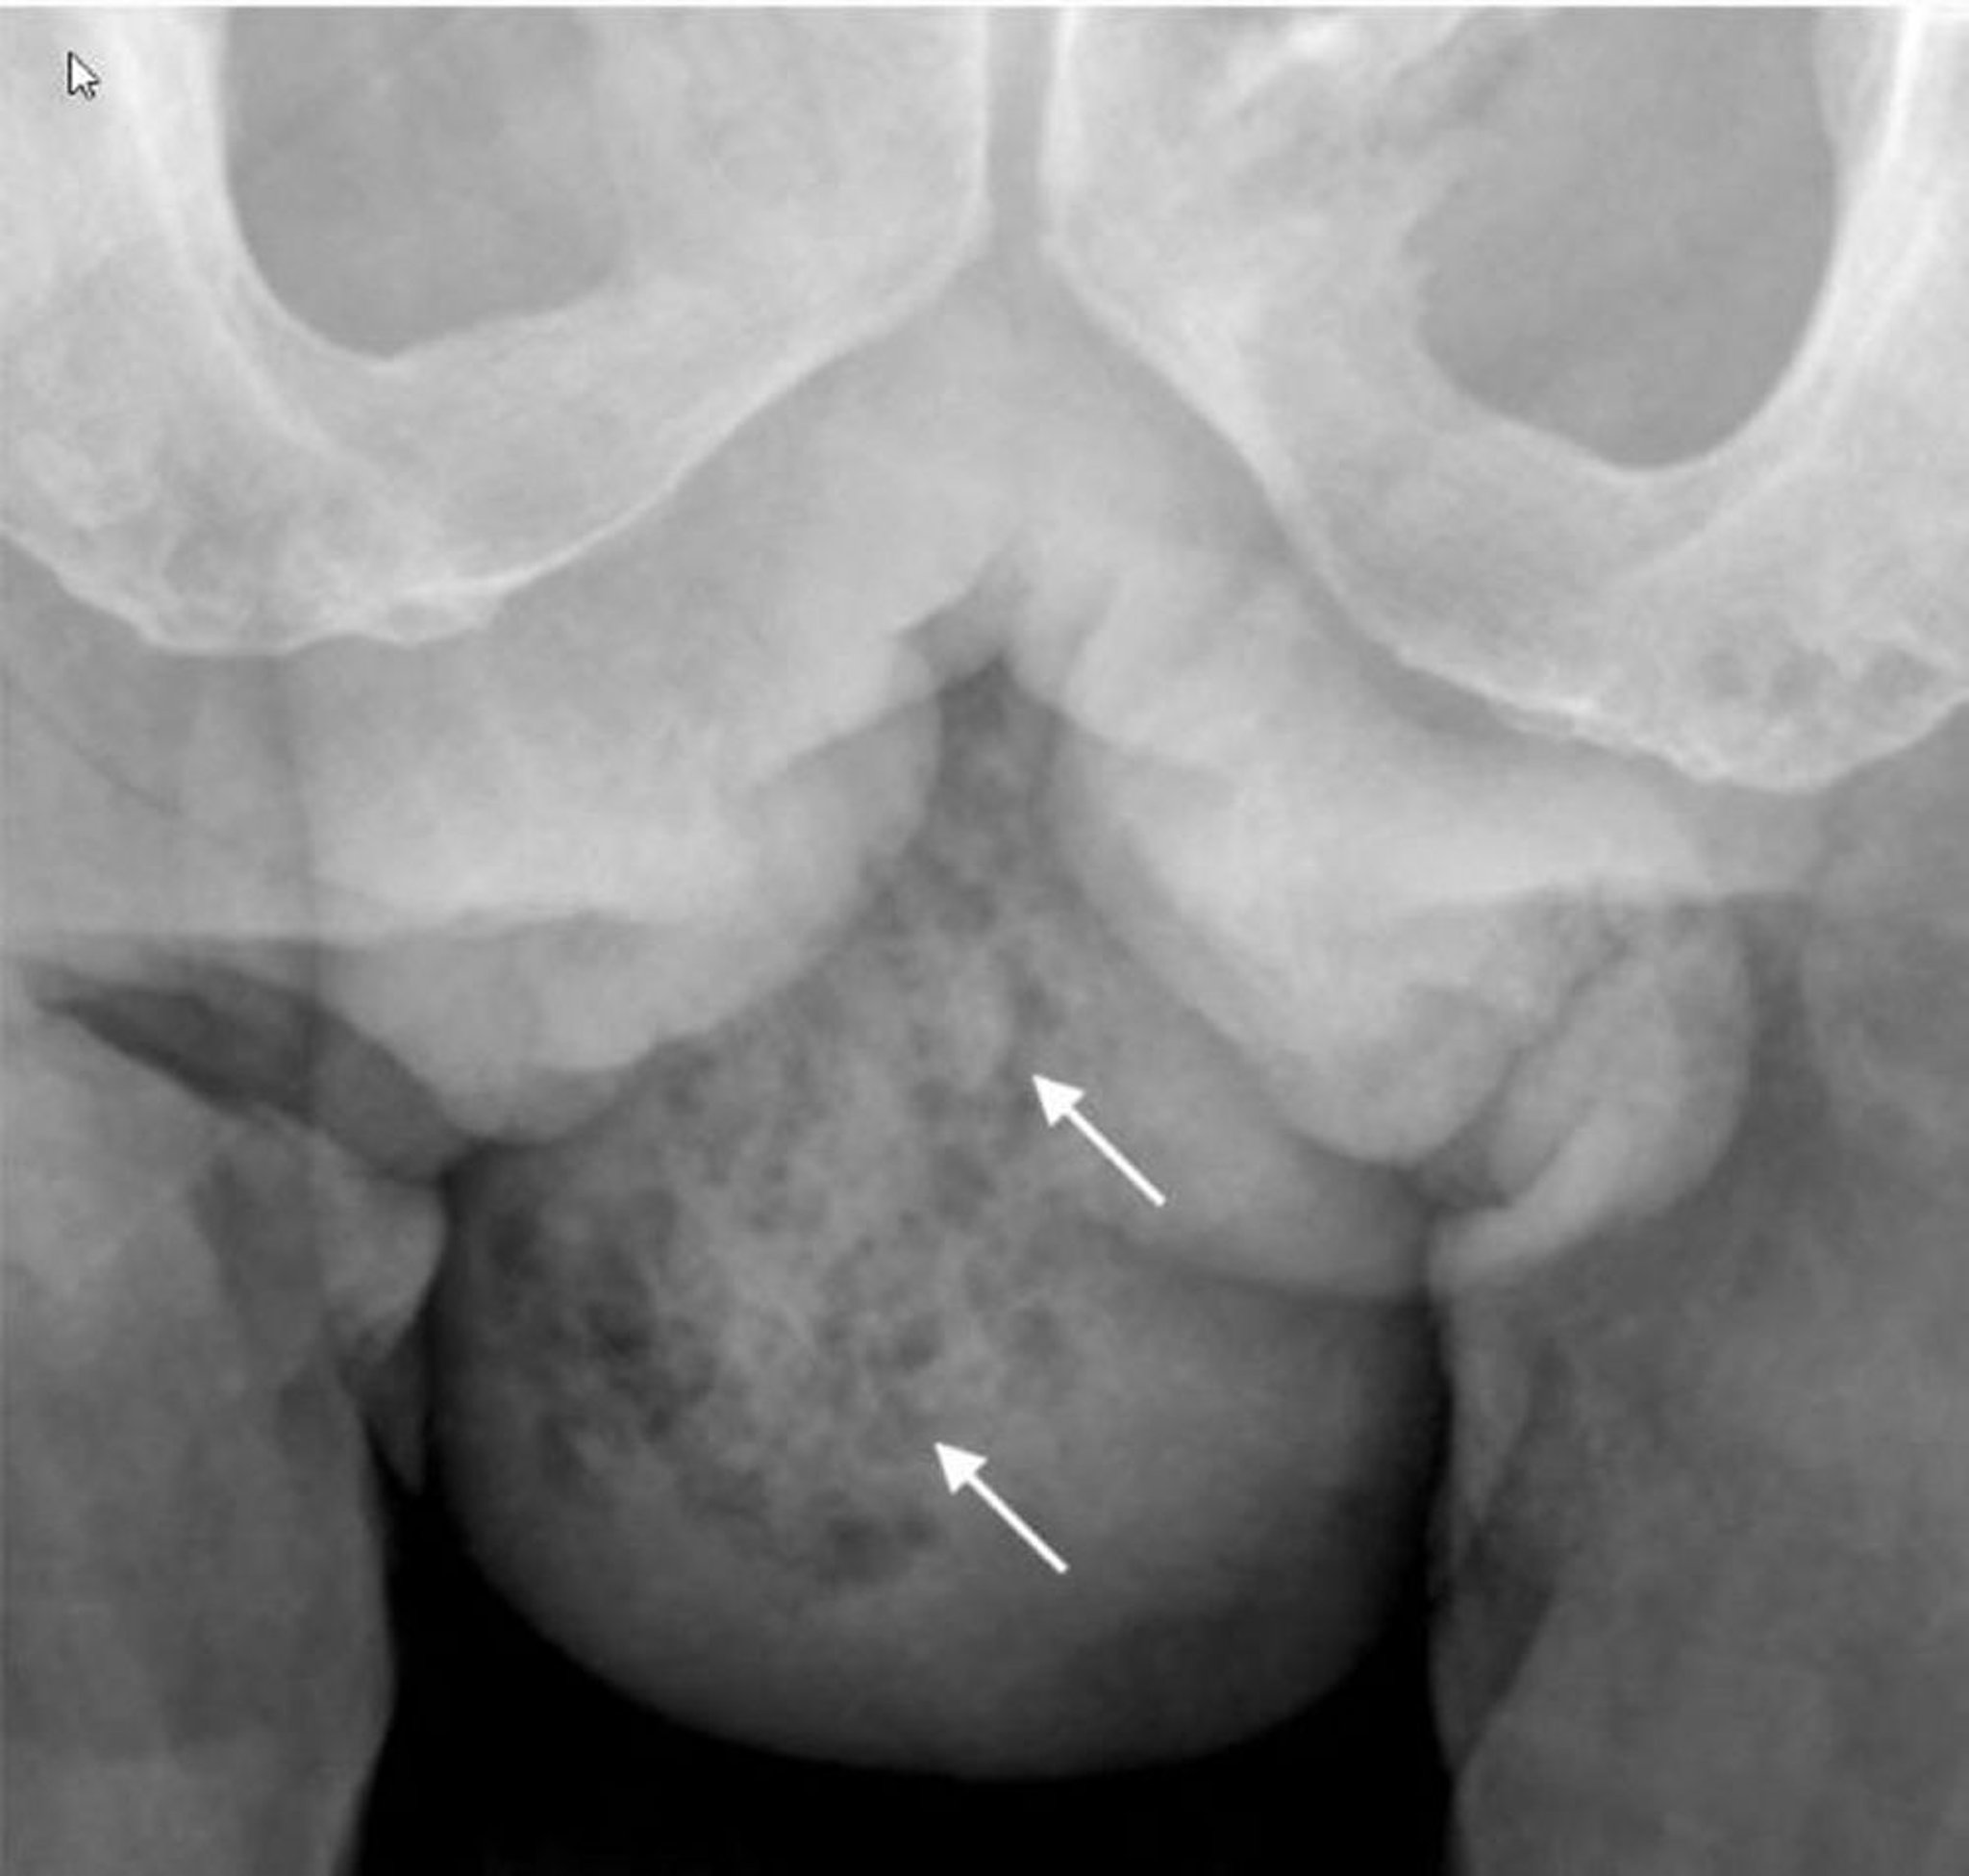

Gangrena di Fournier (radiografia)

Questa radiografia mostra gas nei tessuti molli nell'emiscroto destro (frecce).